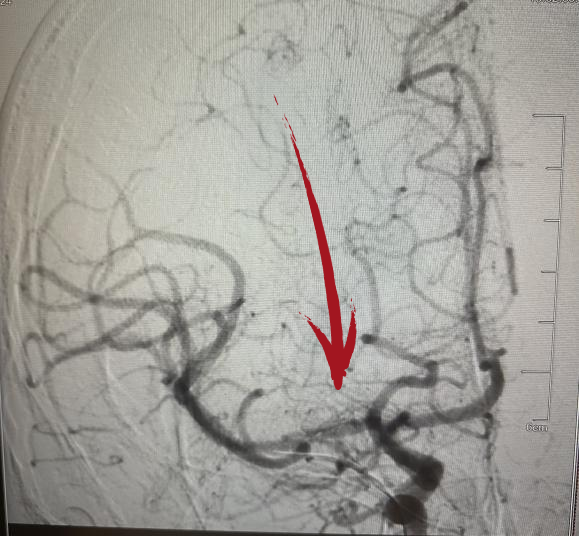

▲术前DSA右侧大脑中动脉起始段闭塞